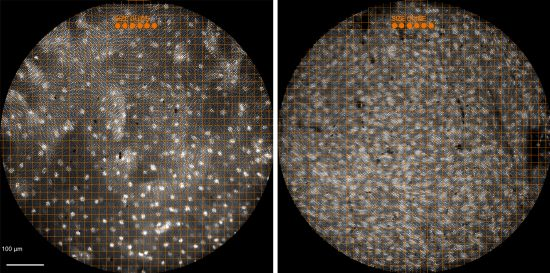

To determine whether a biopsy is needed for a histological exam, health professionals often use endoscopes, small cameras mounted on flexible tubes that can be inserted into the body to visually examine an organ or tissue without surgery. The new high-resolution microendoscope uses a 1-mm-wide fiber-optic cable that is attached to the standard endoscope. The cable transmits images to a high-powered fluorescence microscope, and the endoscopist uses a tablet computer to view the microscope’s output. The microendoscope provides images with similar resolution to traditional histology and allows endoscopists to see individual cells and cell nuclei in lesions suspected of being cancerous. By providing real-time histological data to endoscopists, the microendoscope can help rule out malignancy in cases that would otherwise require a biopsy.